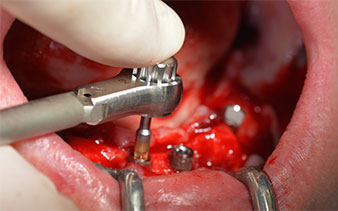

Le protocole chirurgical préconisé pour les implants utilisés (SKY, Bredent Medical) précise une vitesse de rotation de 1.200 tr./min. pour le pré-forage (Fig. 7 - 9).

Ceci correspond à la position suivante prédéfinie dans l'Implantmed. Nous voyons ici le contre-angle W&H tenu à un angle de 45° par rapport à la crête dans la région de 45 afin de préserver le nerf mentonnier. Le trou mentonnier sert de repére anatomique à tous les forages de cette région. Les forages suivants ont été effectués à la vitesse réduite de 300 tr./min. (Fig. 10 et 11).